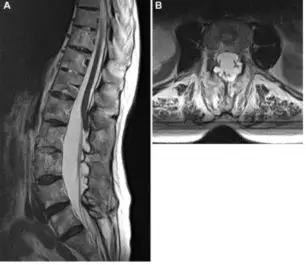

硬膜梭形扩张多发生于胸椎或腰骶椎节段,并导致局部疼痛。神经根或部分圆锥可能粘附在扩张的硬膜壁上,由于栓系效应而出现神经根症状甚至圆锥综合征。MRI检查可以清晰显示硬膜梭形扩张症以及相关的骨性结构的变化(图4)。因为硬膜薄而松弛,所以该型病变直接治疗较为困难。

![]()

图4. 67岁女性患者,既往有强直性脊柱炎病史,出现左下肢感觉异常2年。A.MRI-T2矢状位显示L2-L4的硬膜梭型扩张,圆锥与硬膜粘连;B.MRI轴位示L3水平骨质破坏和多发的小的硬膜囊肿。未建议手术治疗。